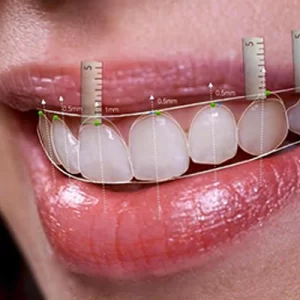

Dişlerdeki renk ve şekil bozuklukları bireyde psikolojik rahatsızlıklara kadar varan problemlere neden olabilir. Diş hekimliğinde estetik ve restoratif maddelerin gelişmesiyle pek çok şekil, renk ve pozisyon bozuklukları rahatlıkla çözümlenebilmektedir. Gülüş Tasarımı işte burada çok önemli bir işlevi üstlenmektedir. Gülüş Tasarımı Nedir? Gülüş tasarımı, hekimlik ve sanatın birlikte uygulanarak, size özel ideal gülüşünüzü yenilemektir. Sizin bir...